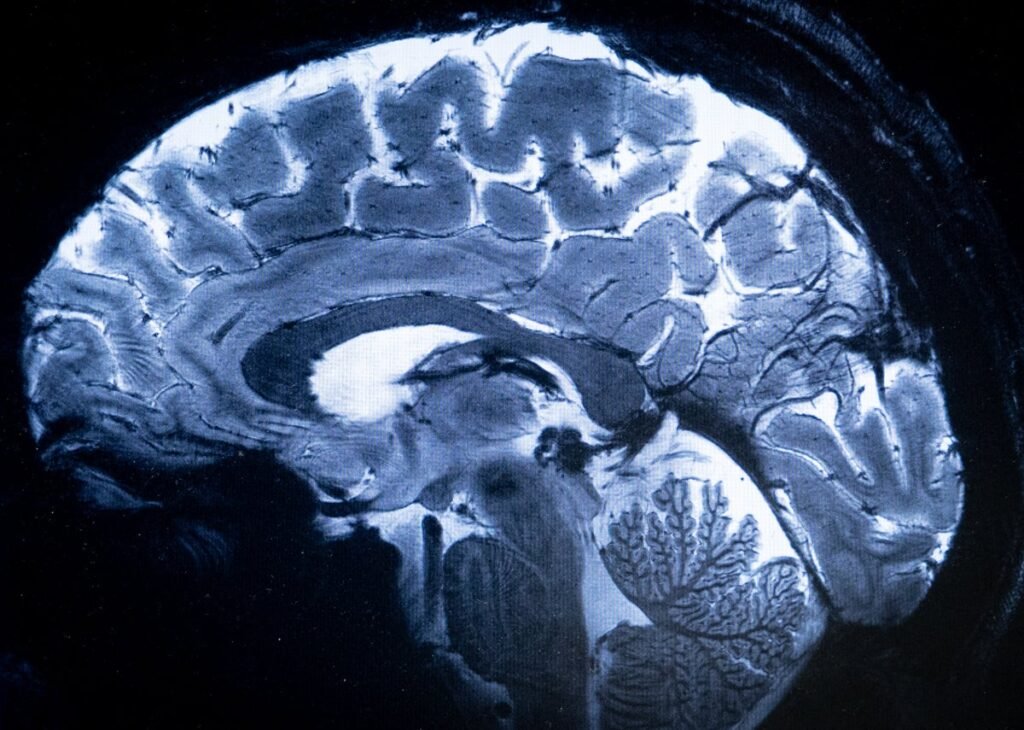

Image of the human brain MRI.

Alain Jocard / AFP via Getty Images